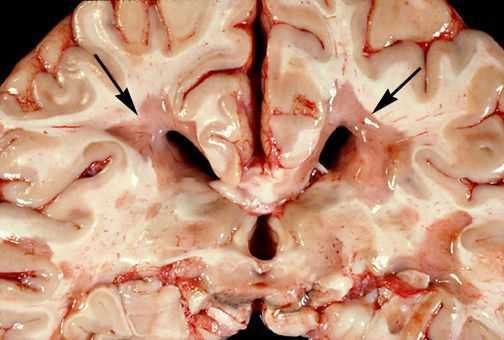

При микроскопическом исследовании обнаруживаются заметные и достаточно характерные изменения, выявляемые с наибольшим постоянством в спинном мозгу, мозговом стволе и полушариях головного мозга. Видны множественные бляшки различной величины (от точечных до весьма массивных, которые, к примеру, занимают весь поперечник спинного мозга), рассеянные преимущественно в белом веществе. Такая множественность и разбросанность очаговых изменений и определяет название болезни.

Отдельные бляшки имеют округлую форму, они нередко сливаются и создают изменения сложных очертаний. Цвет бляшек на разрезе розовато-серый (недавно образовавшиеся очаги) или серый, желтоватый (старые очаги).

При разрезе бляшки определяется их большая плотность по сравлению с нормальной мозговой тканью. Эти уплотнения, склерозирование бляшек дало возможность охарактеризовать заболевание как склероз.

При микроскопии на первый план выступают изменения миелиновых волокон. В области очага, бляшки, в белом веществе наблюдаются в той или иной степени распад миелиновой оболочки, покрывающей нервные волокна центральных проводников, причём осевой цилиндр нередко остаётся неповреждённым.